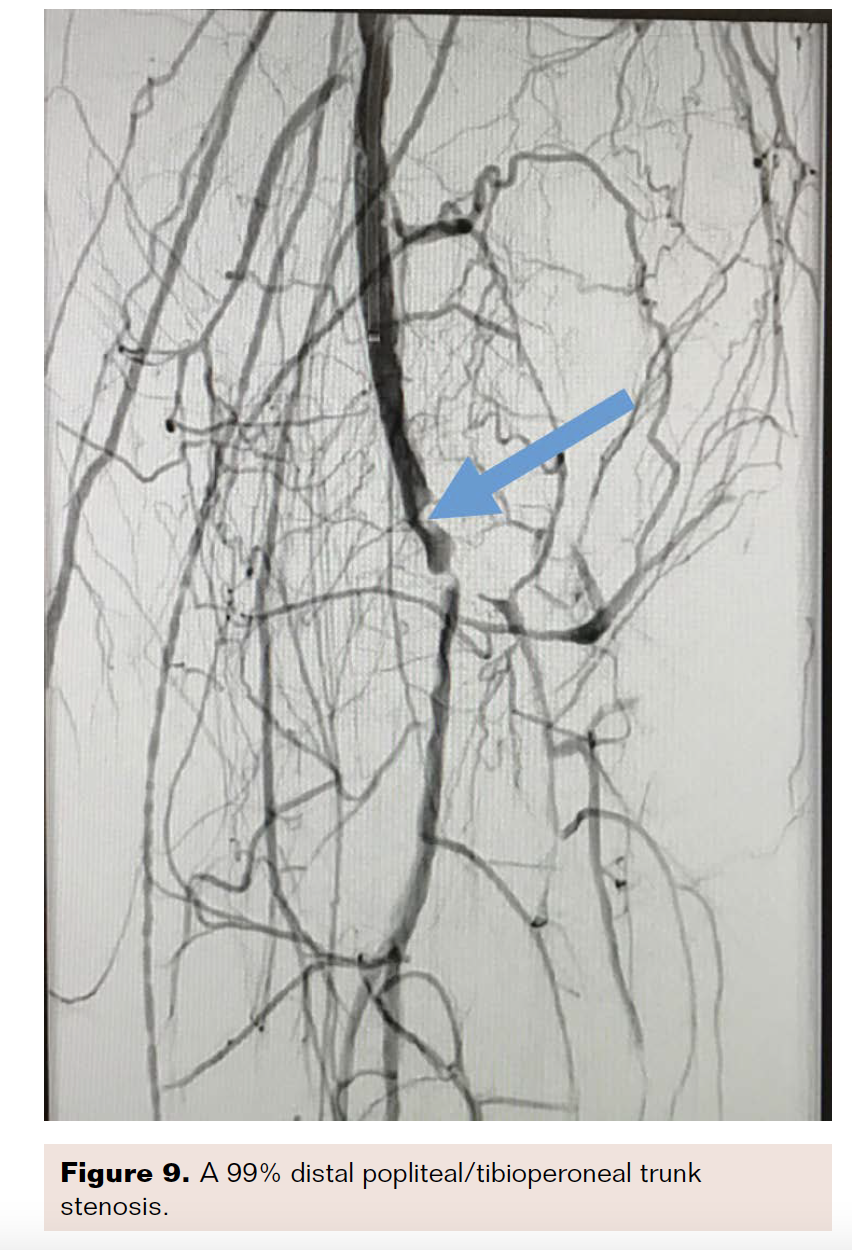

Angiography revealed that the superficial femoral artery (SFA) was occluded in the proximal segment with a short nub (Figure 1) and reconstituted in the mid segment by the profunda collaterals (Figure 2), before becoming reoccluded shortly thereafter and reconstituting in the distal SFA by the profunda collaterals (Figure 3). The P1 and P2 segments of the popliteal artery were patent, but the P3 segment had a short occlusion. The posterior tibial artery and peroneal artery also were patent.